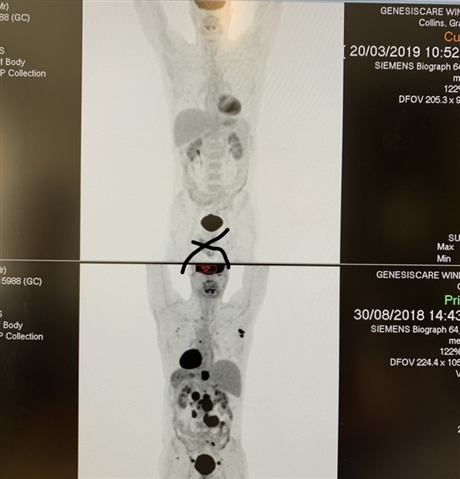

Here is a before and after shot to show just how good this treatment was for me (before on the bottom obviously)

• That's impressive!

I'm waiting for my halfway scan now.  If it were half as good, I'd be thrilled.

• Amazing scan results  hopefully  mine will turn out like that  thanks  for chat  I be in touch